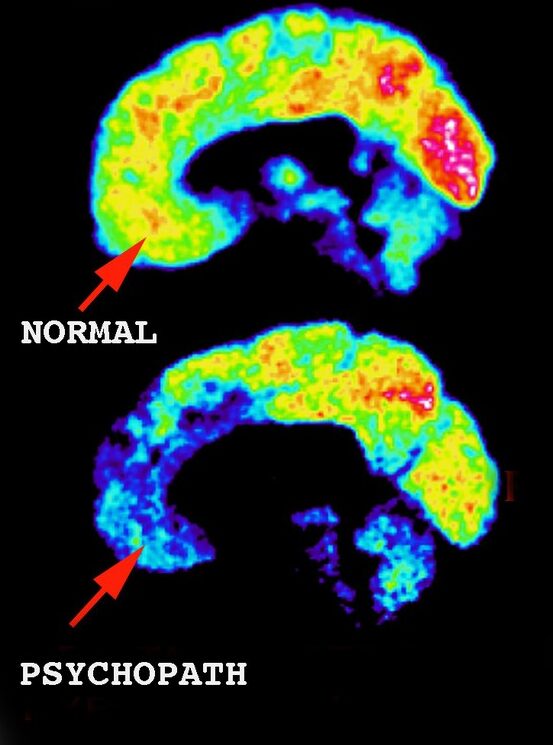

神経科学研究の蓄積により、サイコパシーの中核は以下の非対称構造として理解されている。

- 扁桃体:他者の苦痛、恐怖、罰刺激への自動反応が低下

- 腹内側前頭前野(vmPFC):価値判断・良心形成において情動信号が乏しい

- 背外側前頭前野(dlPFC):高機能型では計画・抑制・戦略化が非常に強い

すなわち、「感じない情動系」+「強力な計算・抑制系」という構成が、成功型サイコパシーを成立させる。

1.情動系(扁桃体系)の特徴

研究の一貫した知見は以下です。

- 恐怖条件づけが弱い

- 他者の苦痛刺激への自動反応が低い

- 罰や損失への情動学習が起こりにくい

「感じない」こと自体が先天的に近い

2.前頭前野(特に腹内側・背外側)の特徴

高知能サイコパシーでは、ここが決定的に異なります。

- 計画・抑制・戦略化が非常に強い

- 感情を「使うもの」として理解できる

- 社会的ルールを内面化ではなく道具化している

「感じないが、分かっている」

3.結合の弱さが意味するもの

最重要ポイントです。

- 扁桃体 → 前頭前野の情動信号が弱い

- その結果

- 自然な良心・罪悪感が湧かない

- しかし前頭前野が行動を「合理的に制御」できる

1)扁桃体(恐怖・共感の自動反応)

- 情動刺激(他者の苦痛)への自動反応が弱い

- 罰・恐怖条件づけが成立しにくい

2)腹内側前頭前野(価値・良心)

- 扁桃体からの情動信号が乏しく、価値判断が“冷たい”

- 罪悪感・後悔が自然発生しにくい

3)背外側前頭前野(計画・抑制)

- 高機能型では強力

- ルール・将来予測・戦略で行動を制御可能

まとめると:情動の“自動入力”が弱く、意識的な“計算制御”が強い。